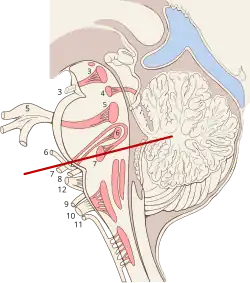

Plan of the facial and intermediate nerves and their communication with other nerves. ("Nucleus of Facial N." labeled at upper left.) | |

The nucleus is situated in the caudal portion of the ventrolateral pontine tegmentum. Its axons take an unusual course, traveling dorsally and looping around the abducens nucleus, then traveling ventrally to exit the ventral pons medial to the spinal trigeminal nucleus. These axons form the motor component of the facial nerve, with parasympathetic and sensory components forming the intermediate nerve.